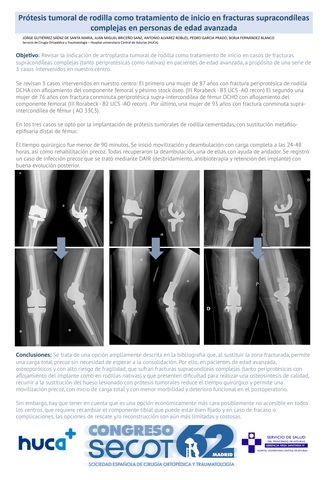

Prótesis tumoral de rodilla como tratamiento de inicio en fracturas supracondíleas complejas en personas de edad avanzada.

JORGE GUTIÉRREZ SÁENZ DE SANTA MARÍA, JUAN MIGUEL BRICEÑO SANZ, ANTONIO ALVAREZ ROBLES, PEDRO GARCIA PRADO, BORJA FERNÁNDEZ BLANCO